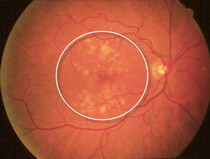

Hastalık büyük çoğunlukla (%85-90) bu tipte görülür. Yaşlanmaya bağlı olarak gelişir ve yavaş ilerler. Görme kaybı yaş tipe oranla azdır ve uzun sürede ortaya çıkar. Makula tabakasının incelmesi veya drusen adı verilen sarı renkte bir maddenin makula üzerinde birikmesi nedeniyle oluşur.Yaş tip:

Kuru Tip Makula Dejenerasyonu

- Detaylı şekilde biyomikroskopta dilate göz dibi muayenesi yapılarak hastalığa özgü drusen, kanama ve eksüdasyon varlığı tespit edilebilir.